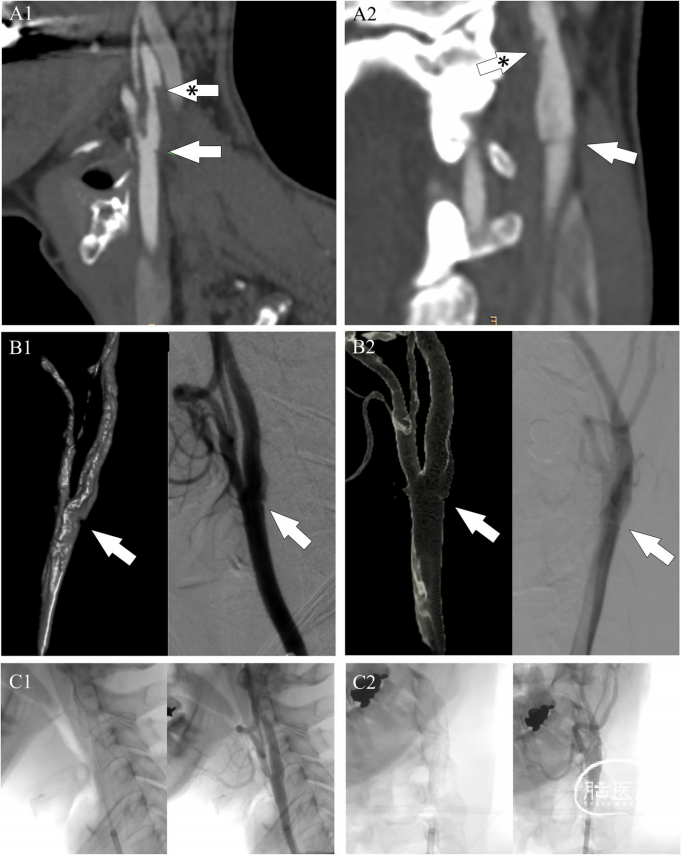

然而,颈动脉2D多普勒超声揭示了可能起源于左侧颈内动脉的非狭窄性低回声斑块的CFFT。CTA证实了CFFT,表现为颈动脉腔内的垂直延长充盈缺损,并在其起源处下方发现了一个类似架状的突出物,表明CaW的存在(图2)。考虑到患者年轻,且中风复发风险极高,于是进行了左侧颈动脉支架置入术(CAS)作为二级预防措施。在抗血栓治疗一周后使用7×40 CGuard支架(Inspire MD,特拉维夫,以色列),覆盖了CaW和CFFT,实现了血管的完全重通(图2)。术中DSA证实了CaW在静脉期造影剂淤滞(图3A-D)。相反,CFFT在DSA上部分消解(图2)。对侧颈动脉未观察到CFFT或CaW,CTA和DSA均未在颅外和颅内血管系统中检测到其他充盈缺损。患者的神经缺损逐渐改善,出院时的神经学检查无异常(NIHSS=0)。

图2. 矢状位CTA(A1)和冠状位(A2)显示:位于颈内动脉的局部缺损与CaW一致(白色箭头);垂直伸长的皮下组织部分附着在颈动脉壁下方,与CFFT一致(星号箭头)。术中DSA和3D重建证实矢状面(B1)和冠状面(B2)投影上存在CaW(箭头)。术后DSA显示矢状面(C1)和冠状面(C2)投影上适当的支架放置和血流恢复。CFFT:颈动脉游离血栓。

图3. 以每秒两帧的速度从矢状位术中DSA获得的连续图像(A-D)显示,造影剂在静脉期停滞在颈动脉蹼中。